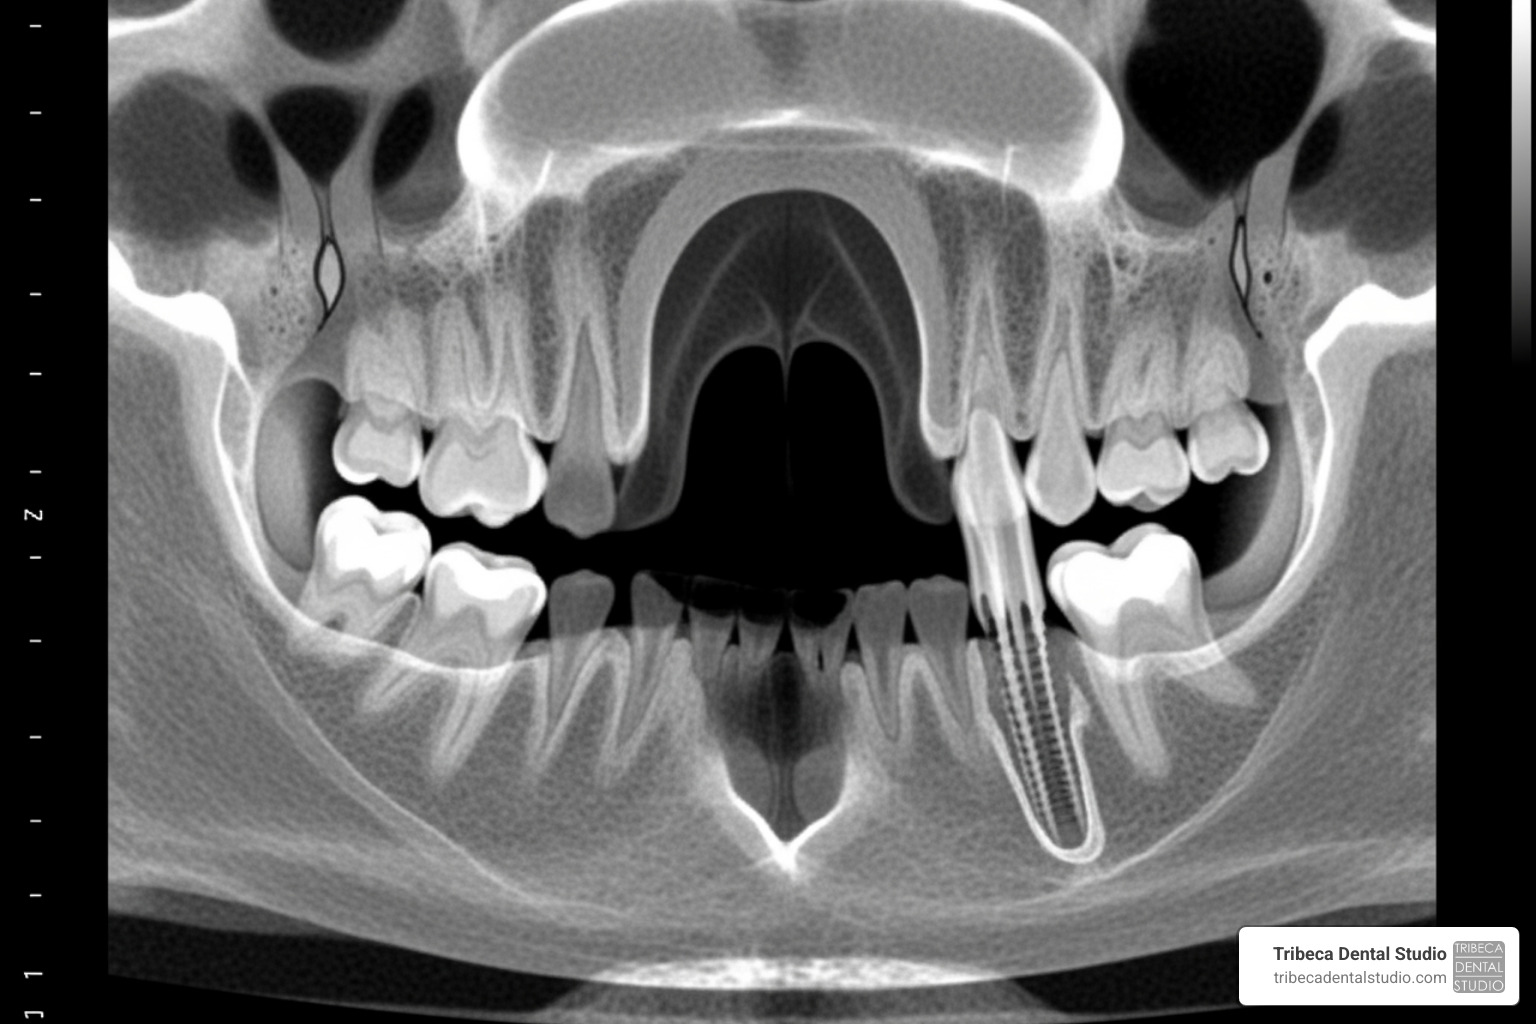

- Insufficient bone height: Diagnostic imaging shows less than 8-10mm of bone between your jaw ridge and the bottom of your maxillary sinus.

Your journey starts with a comprehensive consultation, including advanced 3D CBCT scans. These detailed images allow us to precisely measure your bone, assess your sinuses, and map out the safest and most effective treatment plan. We offer various anesthesia and sedation dentistry options to ensure your comfort throughout the procedure. Our experienced oral surgeons and periodontists are highly skilled in these delicate procedures. For more detailed information on surgical procedures, please visit More info about Oral Surgery.